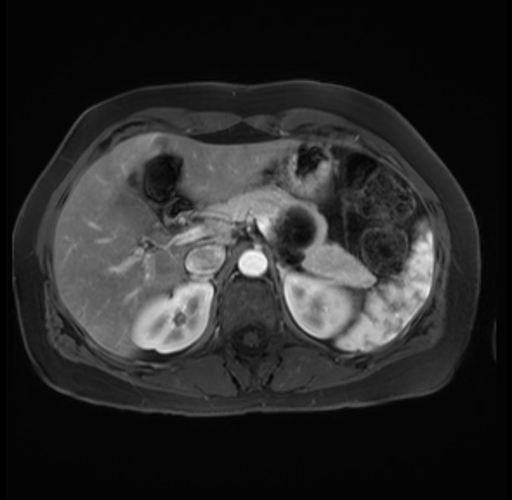

Imaging Analysis

Look through the patient's CT scan to identify any areas of concern for the necessary procedure.

Based on your CT findings, which issue(s) are present and would give reason for "planned slowing down moment(s)" in this case?